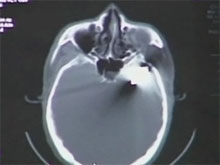

Фото новостиВ Китае хирурги удалили пулю, которая находилась в голове фермера Ван Тяньцин из китайской провинции Хэбэй на протяжении 23 лет.

Как сообщается, мужчина обратился к медикам в связи с участившимися случаями судорог, которые изредка беспокоили его в течение 20 лет. Врачи, сделав пациенту компьютерную томографию головы, обнаружили в полости черепа пулю.

По словам нейрохирурга Вана Чжимина, пуля пробила череп фермера и застряла в правой височной части. Как пояснил медик, если бы мужчина сдвинулся немного вправо и назад, то он бы, скорее всего, не выжил.